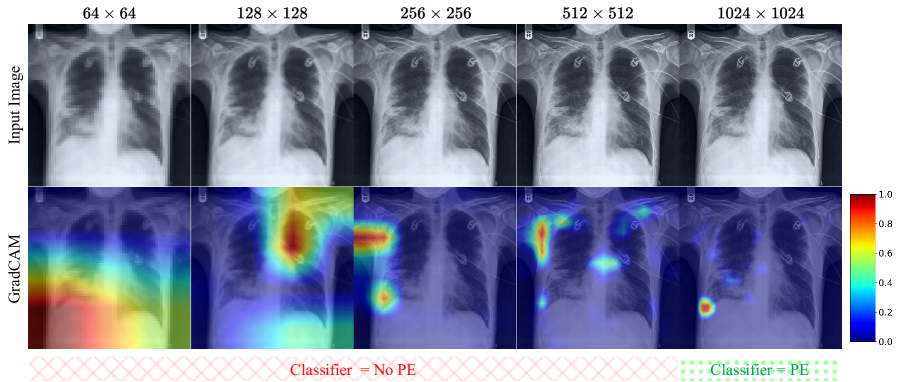

High-resolution medical images are needed for many clinical decision support systems that depend on the ability to resolve fine-grained anatomical and pathological features. Consider its importance in the context of chest X-rays, where subtle abnormalities—such as small pulmonary nodules, fine patterns, or early pleural changes—are more easily identified at higher resolutions Haque et al. (2023); Jiang et al. (2025). AI-driven diagnostic systems should maintain images at high resolution, if available, in order to preserve essential texture and edge information that might otherwise be lost at lower resolutions Miyata et al. (2020); Schuijf et al. (2022); Yanagawa et al. (2018). For instance, in detecting pleural effusion, the separation of the pleural line—a key diagnostic indicator—may remain undetectable at lower resolutions but becomes visible when sufficient spatial detail is present (see Figure 1 & 2). Given their importance, high-resolution image generators can synthesize detailed medical images in contexts where real, high-quality data is scarce, thereby supporting the development of robust diagnostic models in data-limited settings.

Figure 1: Grad-CAM visualization of activation maps in the EfficientNet classifier for pleural effusion (PE) classification of a patient’s Chest X-ray image Irvin et al. (2019). The heatmaps highlight that the model fails to focus on relevant regions in low-resolution images, leading to incorrect classifications. At the higher resolution, the model focuses on the exact location of interest.